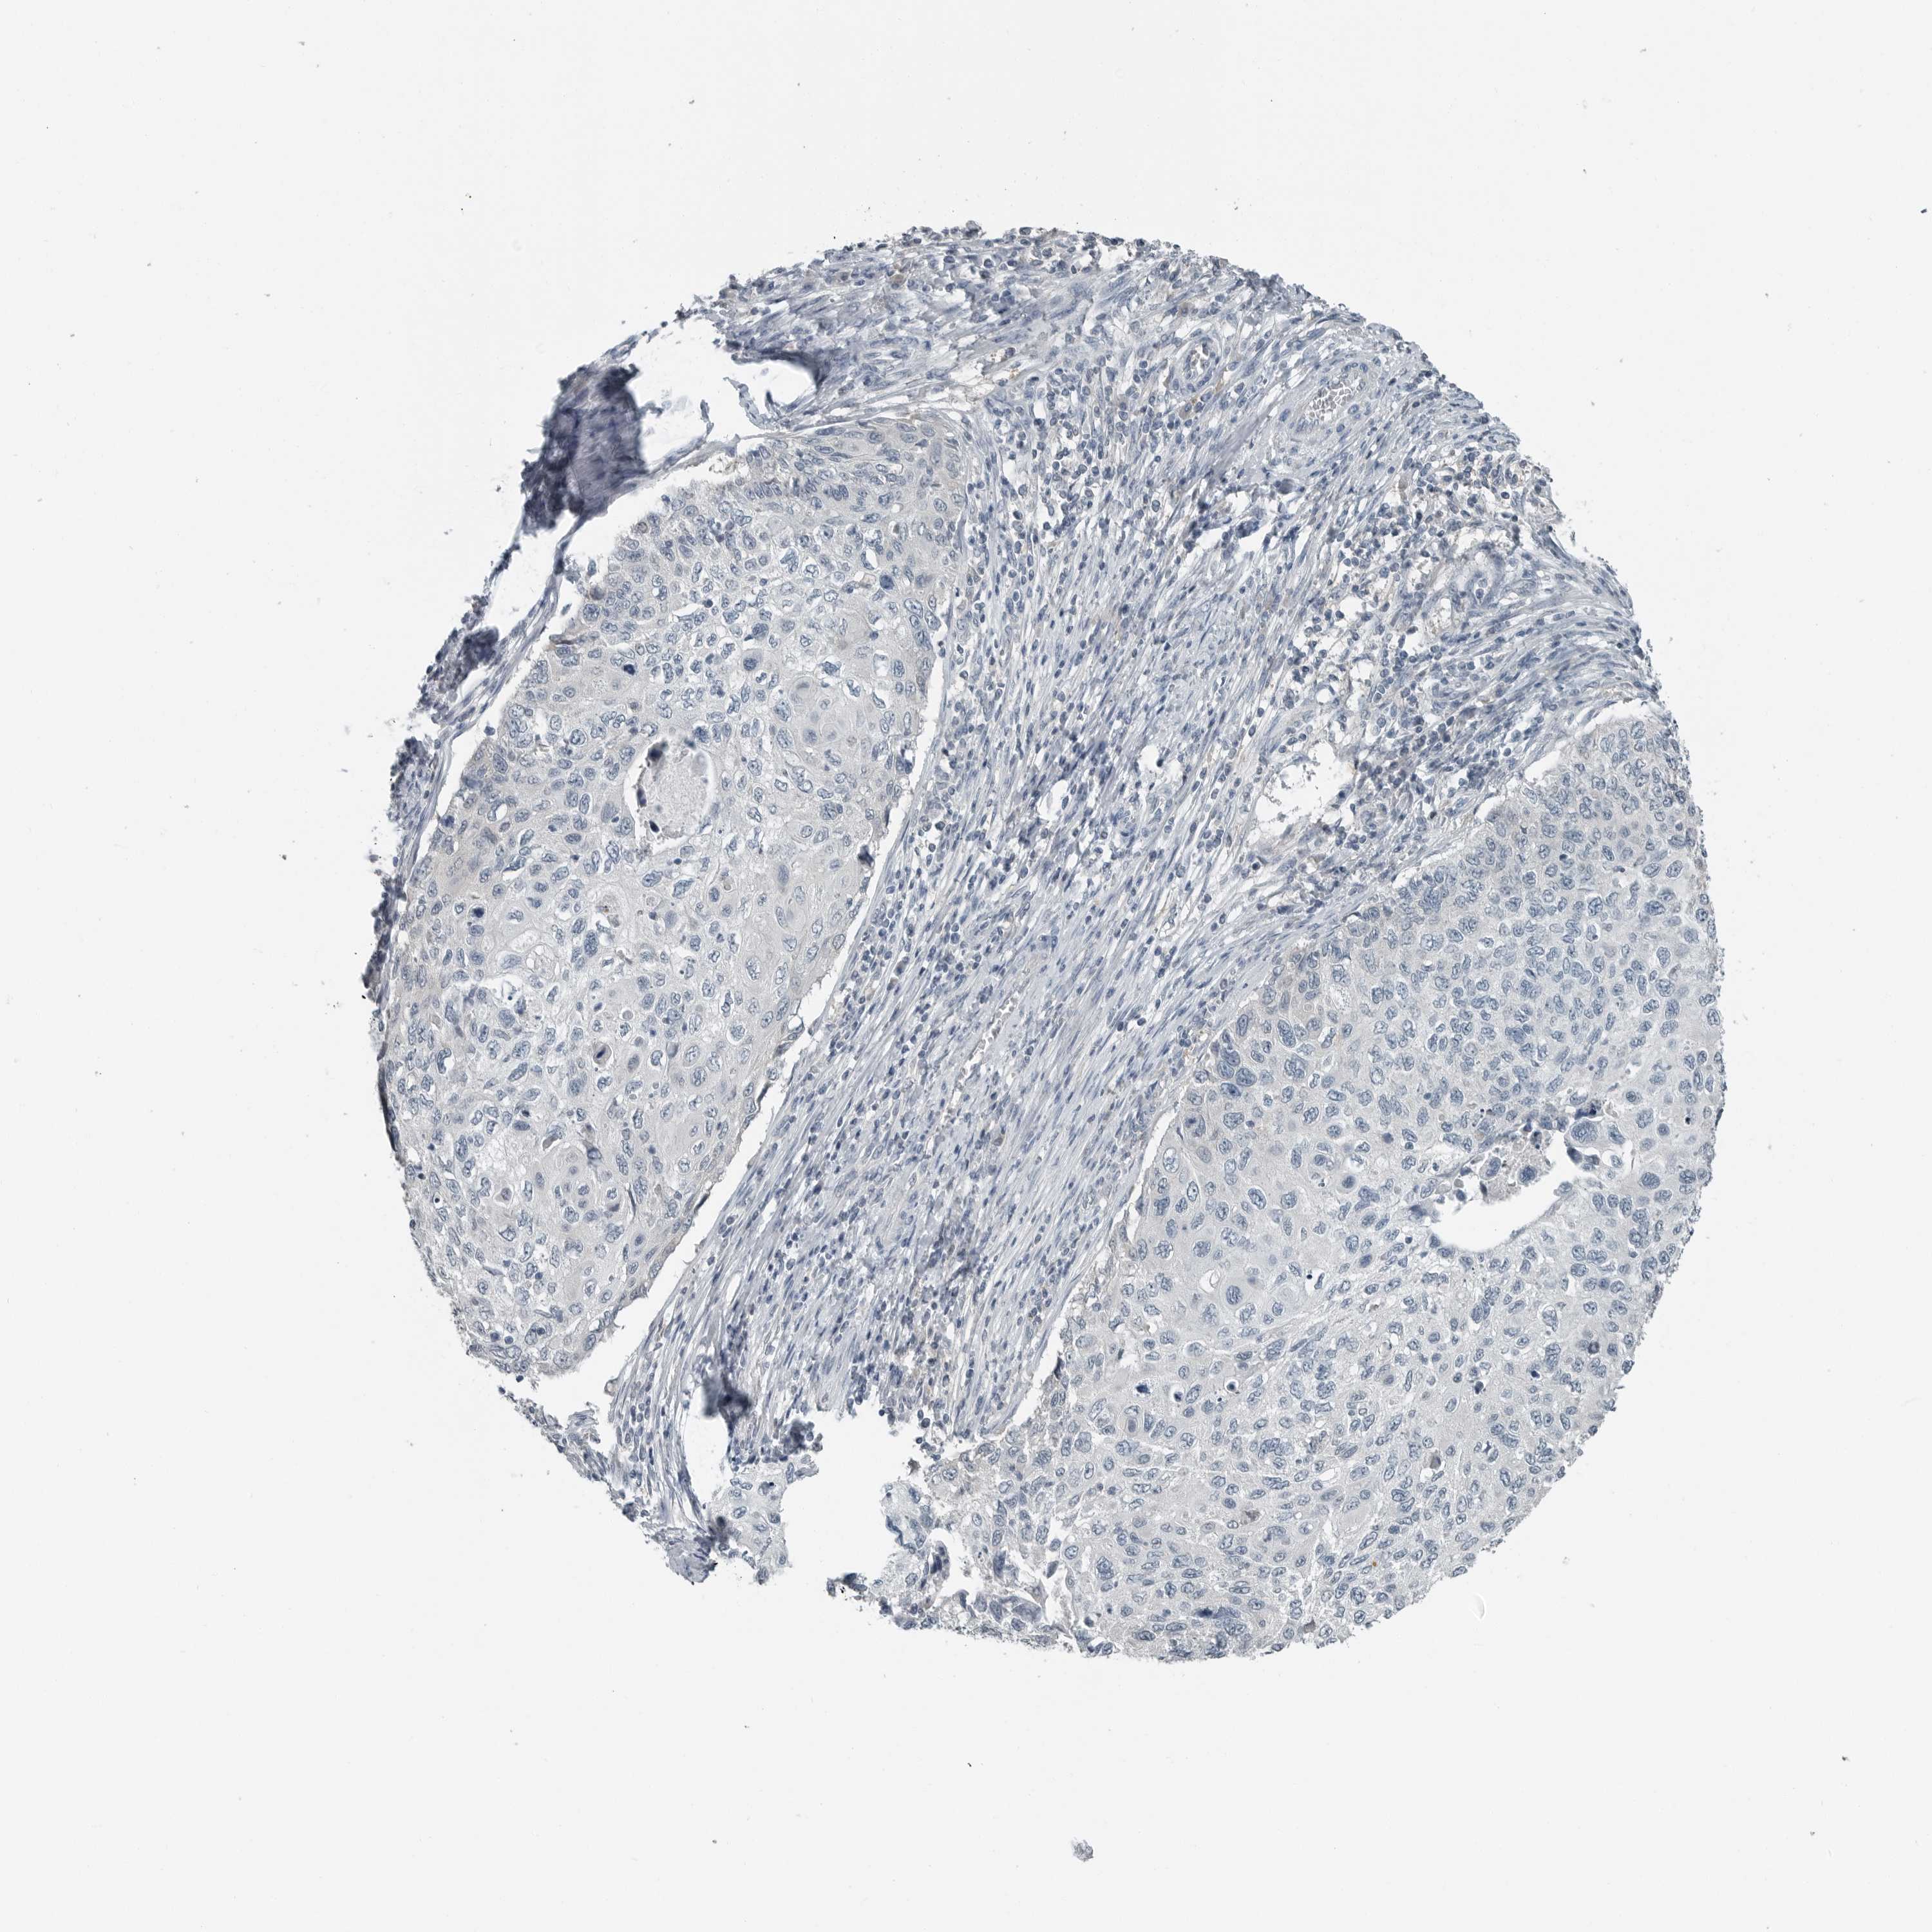

CERVICAL CANCER - Protein expressioni

A mouse-over function shows sample information and annotation data. Click on an image to view it in a full screen mode. Samples can be filtered based on level of antibody staining by selecting one or several of the following categories: high, medium, low and not detected. The assay and annotation is described here.

Note that samples used for immunohistochemistry by the Human Protein Atlas do not correspond to samples in the TCGA dataset.

Antibody stainingi

Antibody staining in the annotated cell types in the current human tissue is reported as not detected, low, medium, or high, based on conventional immunohistochemistry profiling in selected tissues. This score is based on the combination of the staining intensity and fraction of stained cells.

Each image is clickable and will lead to virtual microscopy that enables deeper exploration of all samples and also displays staining intensity scores, fraction scores and subcellular localization as well as patient and tissue information for each sample.

Antibody HPA021176

Antibody HPA021177

Antibody HPA027736

Squamous cell carcinoma, NOS

Adenocarcinoma, NOS